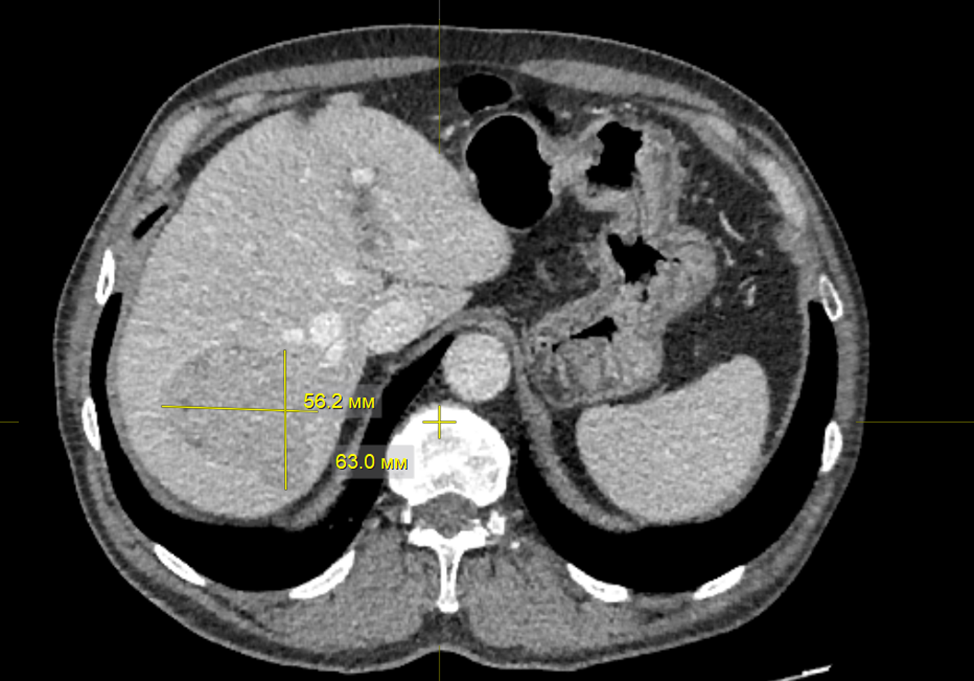

1. Рис. 1. КТ органов брюшной полости. В S7 печени определяется гиперваскулярное образование с нечеткими неровными контурами, размерами 63×56×49 мм, с наличием псевдокапсулы в отсроченную фазу, плотность +40 – + 47 HU, контраст накапливает неоднородно до +94 HU. Примечание: рисунок выполнен авторами | |